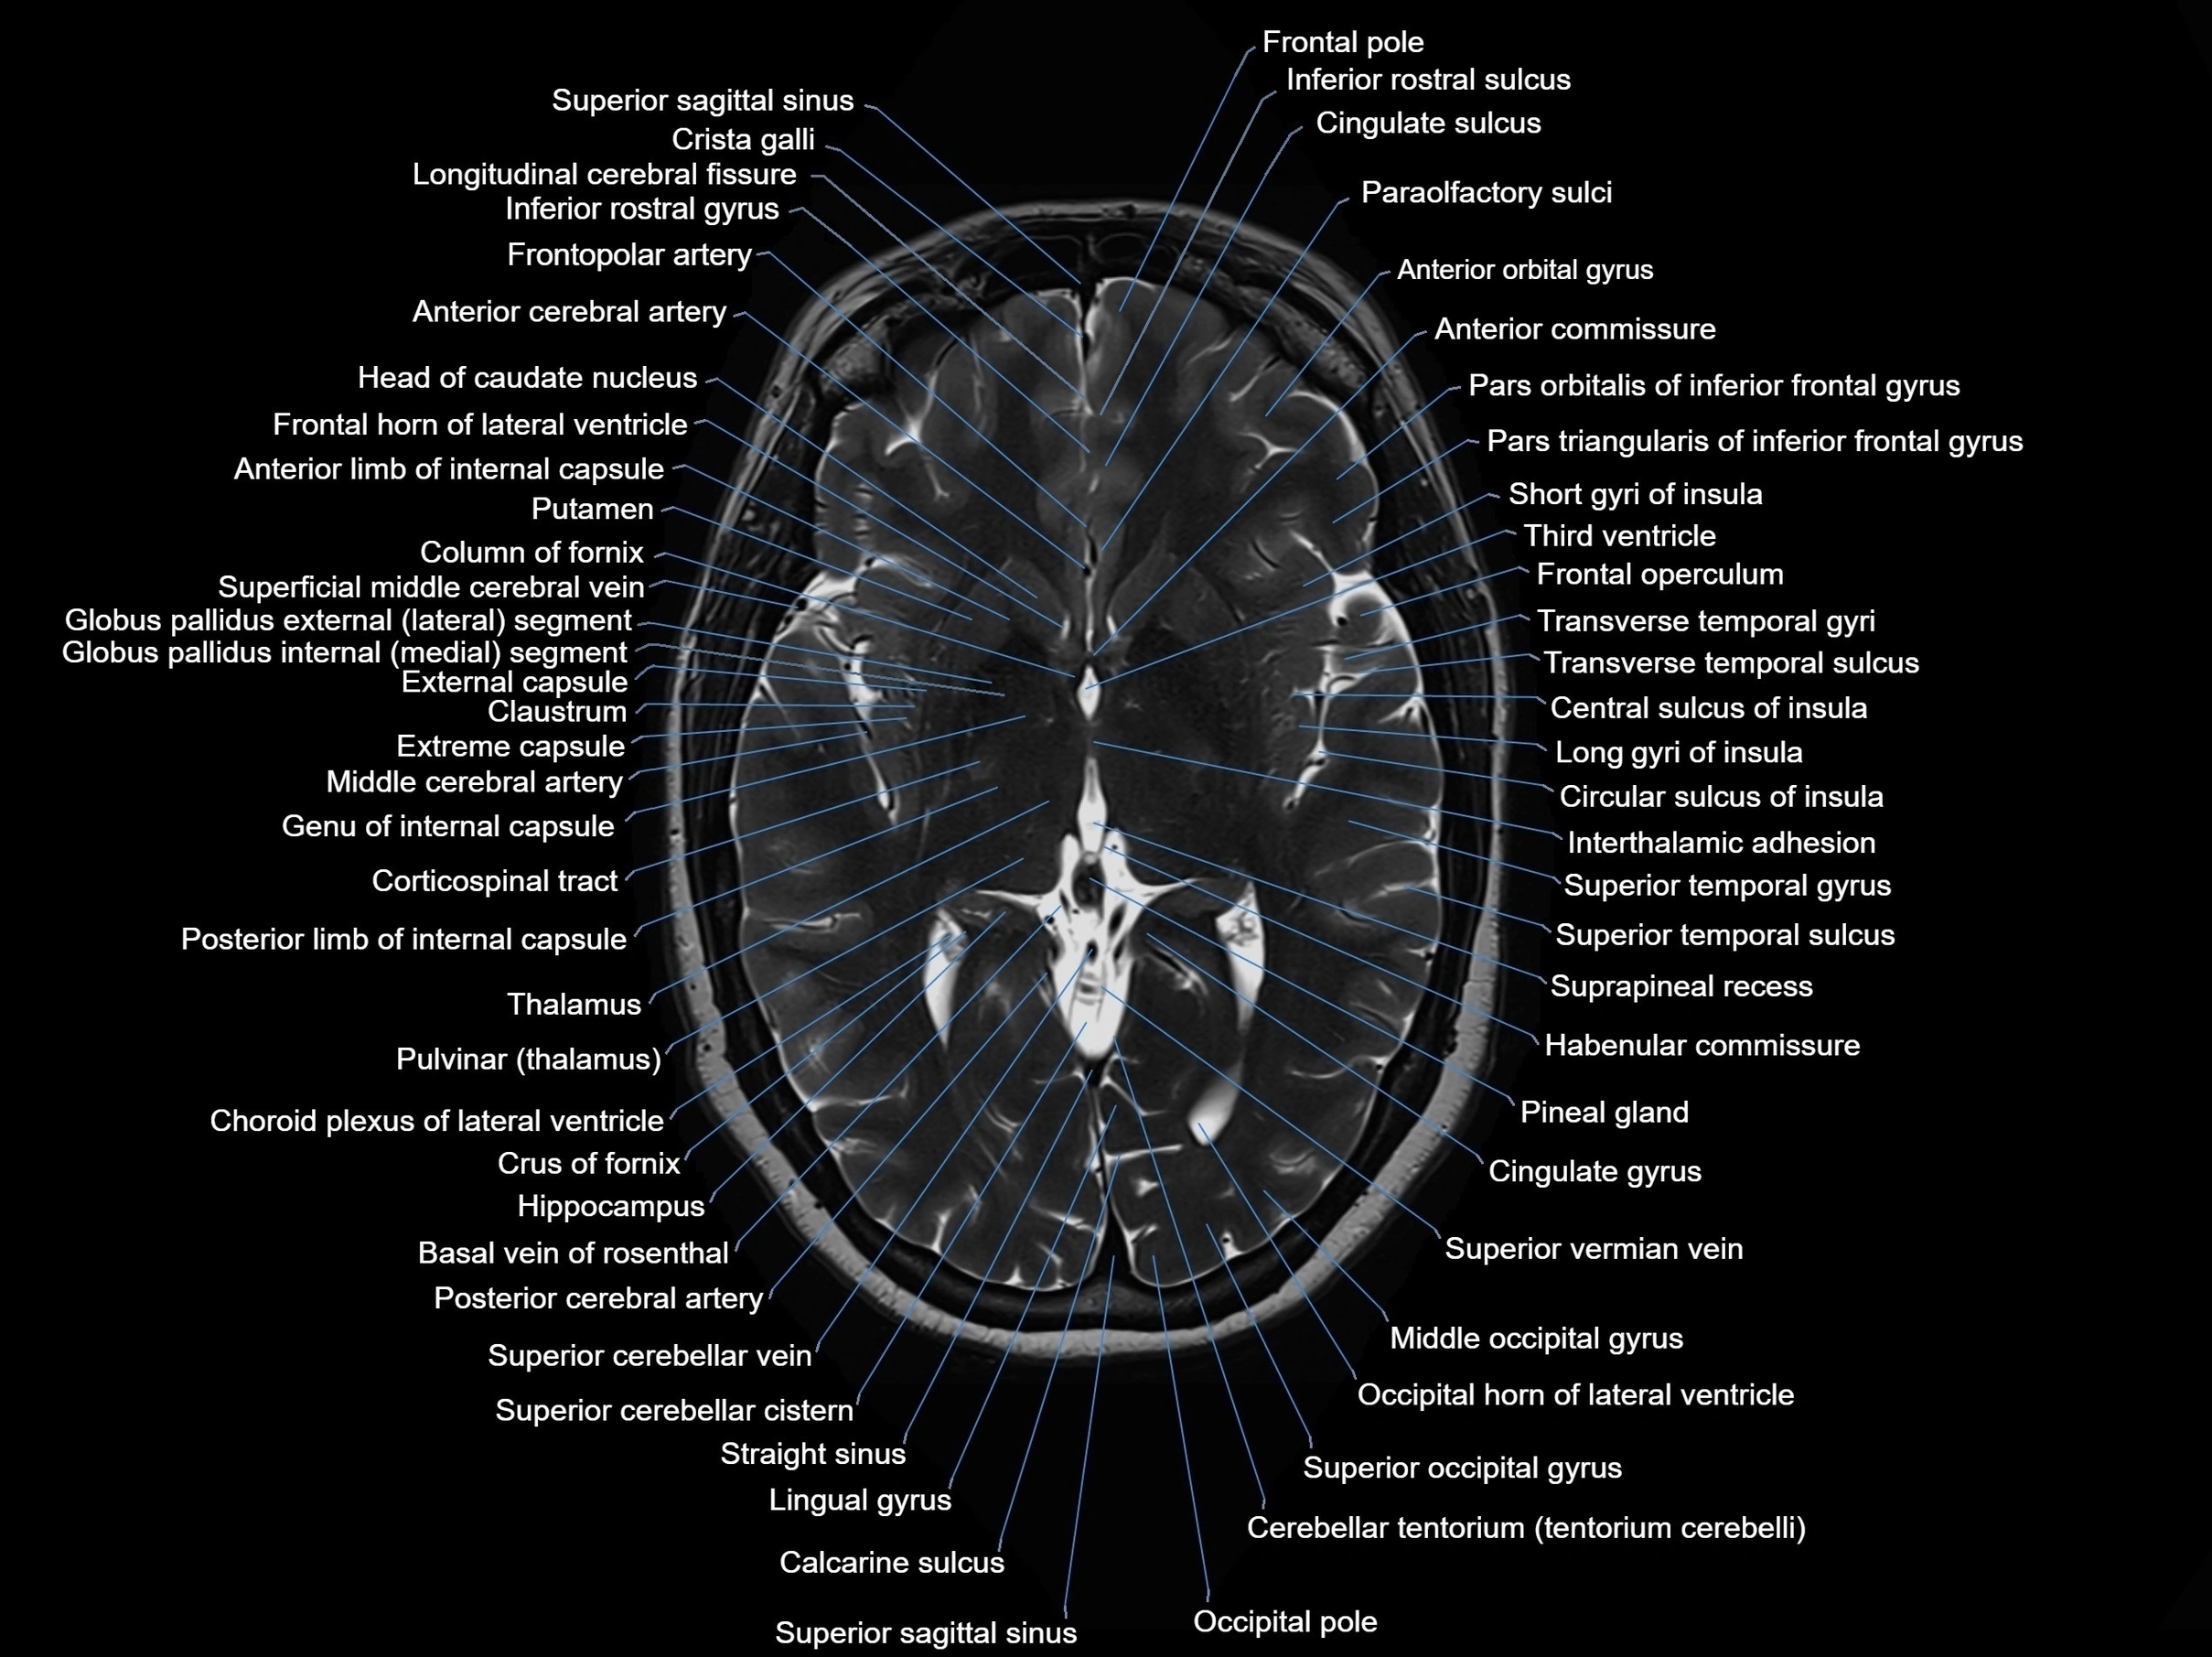

MRI images